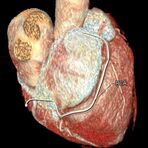

Herz

Durchführung am Standort im Diakonissenkrankenhaus

Die Computertomographie ermöglicht einen vielfältigen Einsatz. Es können Aufnahmen von Kopf bis Fuß in höchster Bildqualität erstellt werden. Eine Stärke der Methode liegt z. B. in ihrer Schnelligkeit. Deshalb wird sie häufig in der Notfalldiagnostik eingesetzt, aber auch bei der Darstellung von Körperbereichen, die ständig in Bewegung sind, wie z. B. die Lunge und das Herz. Außerdem eignet sie sich deshalb auch für die Untersuchung von schwer kranken, wenig belastbaren Patienten.